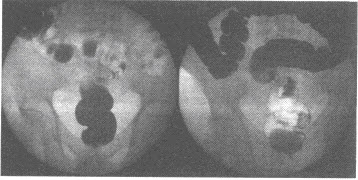

�У�5�꣬���ײ���ʹ2�ܣ�CTƽɨMPRͼ�����£�����ܵ�����ǣ���

�У�7�꣬��ǰ����ʹ20�죬����ʱƤ�½ϸߣ����´�39�档ʵ���Ҽ�飺WBC��12.05×10/L��������ϸ��79%���ҳ��������λDRƬ��ͼ